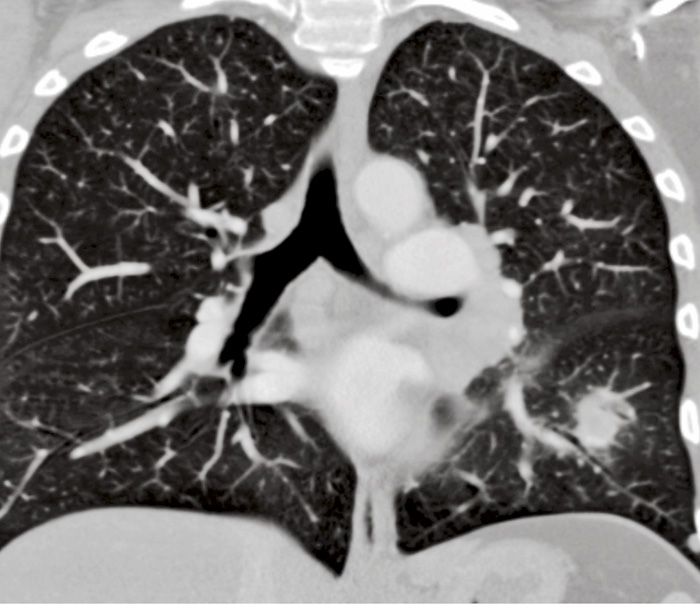

Figur 1A. 66-årig man med lungförändringar orsakade av tularemi (Fall 1). Koronart snitt från datortomografi som visar en förtätning i vänster underlob.

Figur 1B.  Tvärsnitt från datortomografi som visar förtätningen i vänster underlob respektive lymfkörtelför­storing i väns­ter lunghilus.

Fallet rör en 66-årig icke-rökande jordbruksarbetare som sökte för flanksmärta. Datortomografi (DT) visade en 2 cm stor förtätning i vänster underlob och körtelförstoringar i vänster lunghilus (Figur 1), varför patienten remitterades till lung- och allergikliniken och ingick i en s k snabbspårsutredning vid misstänkt lungcancer.

Kombinerad undersökning med PET och DT visade FDG-upptag både i den misstänkta tumören och i mediastinala lymfkörtlar. Infiltratet hade dock minskat något jämfört med föregående datortomografi, och bronkoskopi visade enbart makro- och mikroskopisk inflammation. Senare framkom att patienten haft en feberepisod ett par veckor innan han sökt läkare, men han var nu feberfri. Serologi för tularemi blev starkt positiv, och förändringarna läkte successivt ut helt.